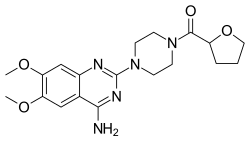

| Terazosin | Hytrin |

|

Competitive blocking of α1 receptor.[10] | Lowers blood pressure.[2] | ||